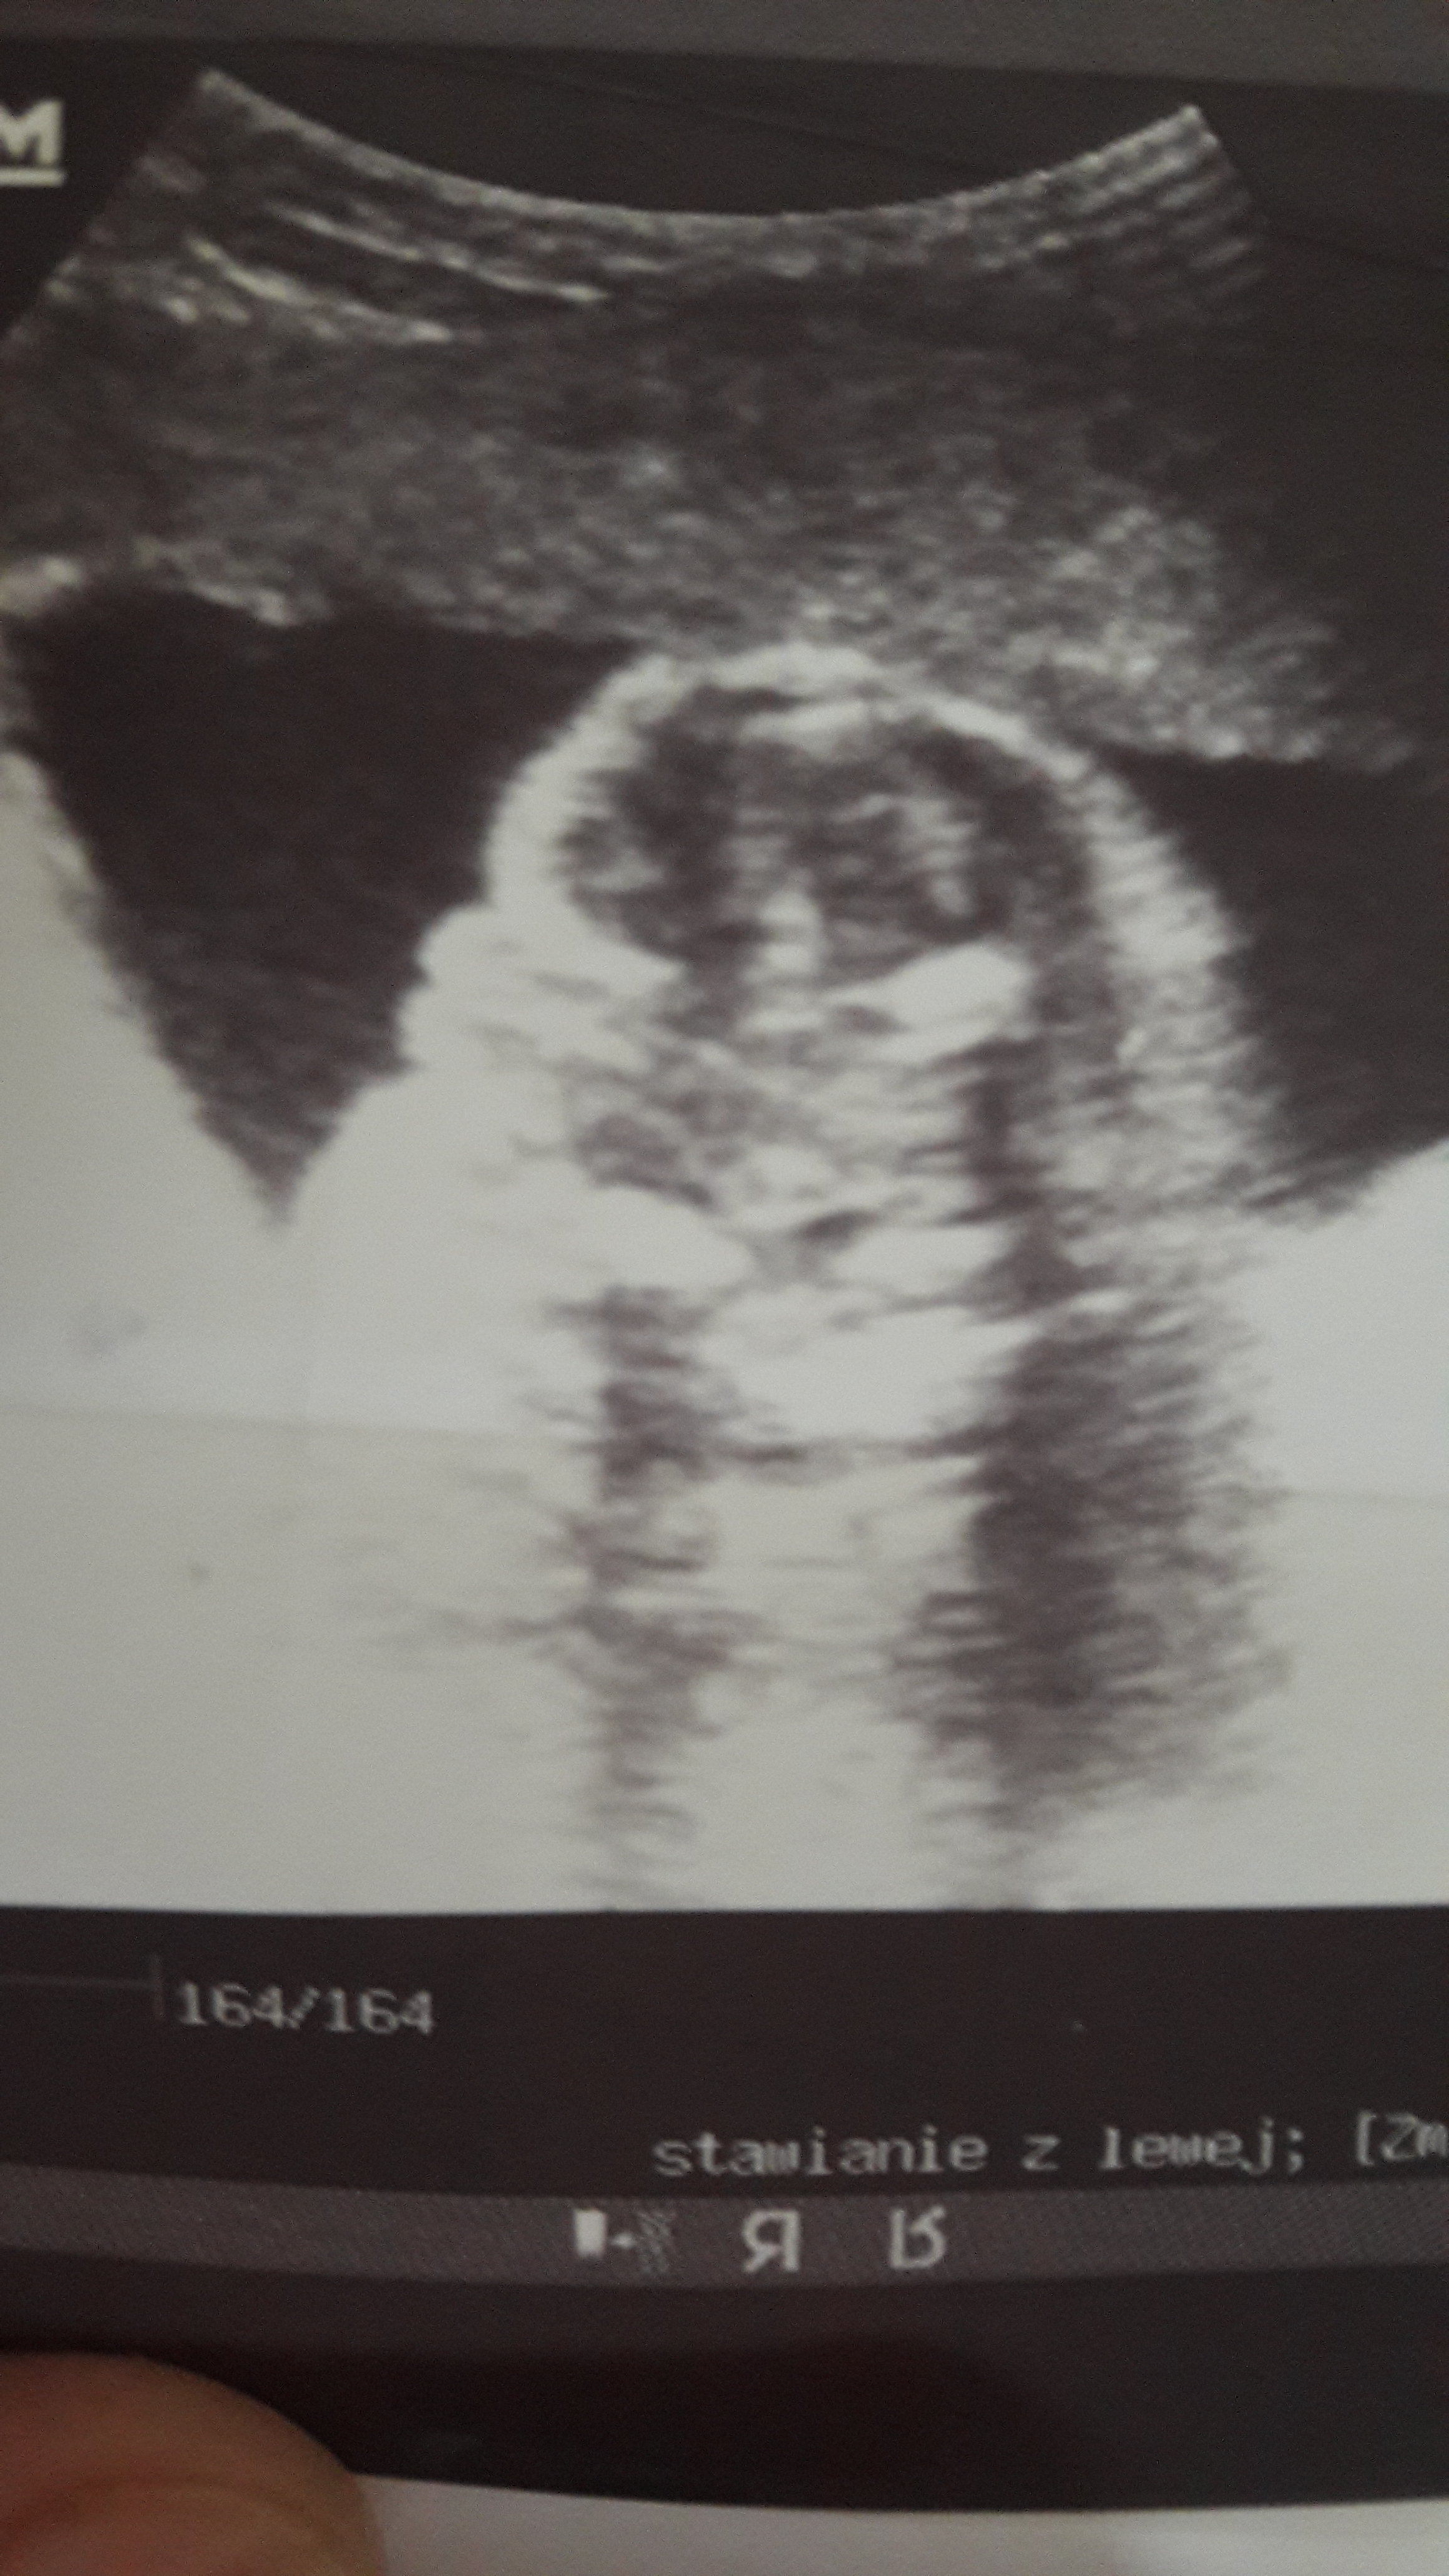

Usg chłopak czy dziewczynka

Witam w 19 tygodniu ciąży dowiedziałam się ze będę miała dziewczynkę w 20 tyg okazało się jednak , że to chłopak. Sama już nie wiem bo na jednym usg widać na pewno dziewuche a na drugim chłopca. Może to pempowina ?? Może ktoś mi pomoże rozwiązać ta zagadkę

Załączniki

• 4A8F5FF1-76CA-4DE0-AC12-5EDF08E820F2.jpg

4A8F5FF1-76CA-4DE0-AC12-5EDF08E820F2.jpg

596,4 KB · Wyświetleń: 43 699